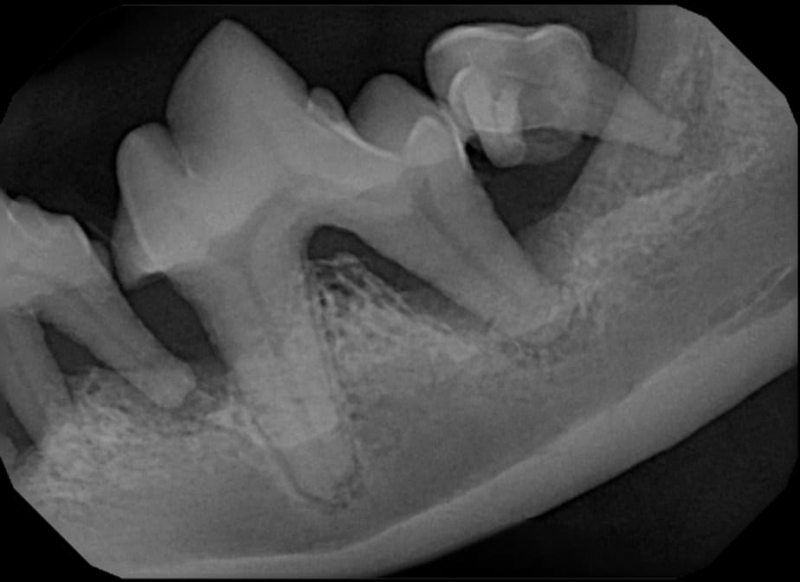

The Center now provides advanced imaging via cone beam CT. Cone beam CT is excellent for visualization of bony structures of the skull, nasal cavity, teeth, and ears. Cone beam CT is especially helpful for diagnosing dental disease and evaluation of jaw fractures. It can also be useful for evaluating the sinuses and tympanic bulla. Cone beam CT can be used in conjunction with nasal biopsy and culture to evaluate nasal discharge whether chronic or acute.

Pets can be involved in trauma that can cause fractures to their head, teeth, and jaw bones. Correctly repairing these fractures is extremely important for your pet to have normal function of their mouth. If a jaw fracture is allowed to heal in an abnormal position, your pet may have great difficulty chewing and can be in significant pain. Many fractures can be successfully treated with minimally invasive oral procedures, but more complicated cases may require bone plating techniques. The Center offers cone beam CT imaging which provides extremely detailed images of the bones of the head and skull. Advanced imaging with CBCT facilitates selection of the best surgical technique to get your pet back to eating and comfort as soon as possible.